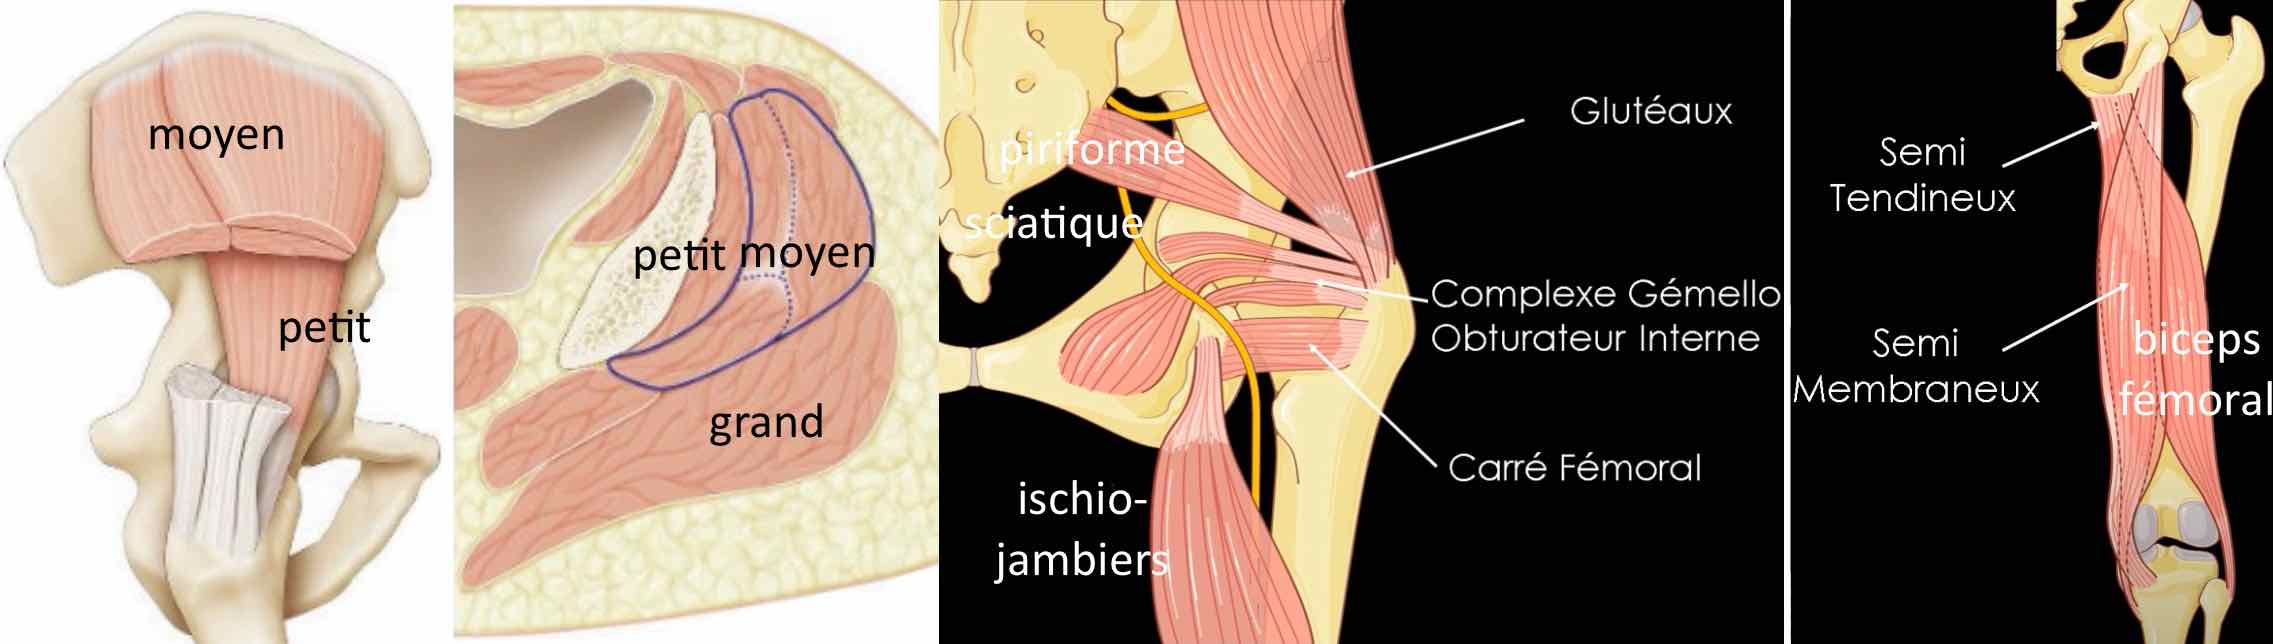

Intégrité du muscle droit fémoral et de ses insertions tendineuses.

Intégrité des tendons glutéaux et de l'insertion proximale des ischio-jambiers.

Respect des tendons du biceps fémoral et de la patte d'oie.

Bandelette ilio-tibiale sans particularité.